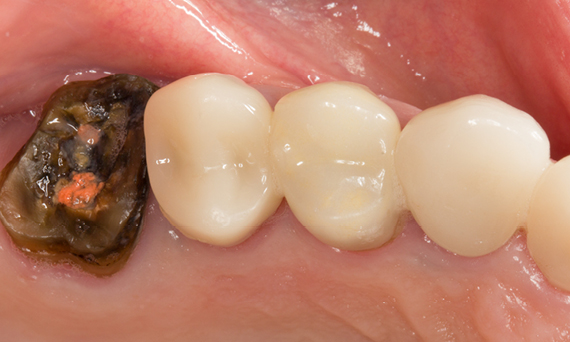

Before

A large carious mesial lesion on tooth 15. The tooth showed asymptomatic apical periodontitis and a significant loss of tooth structure.